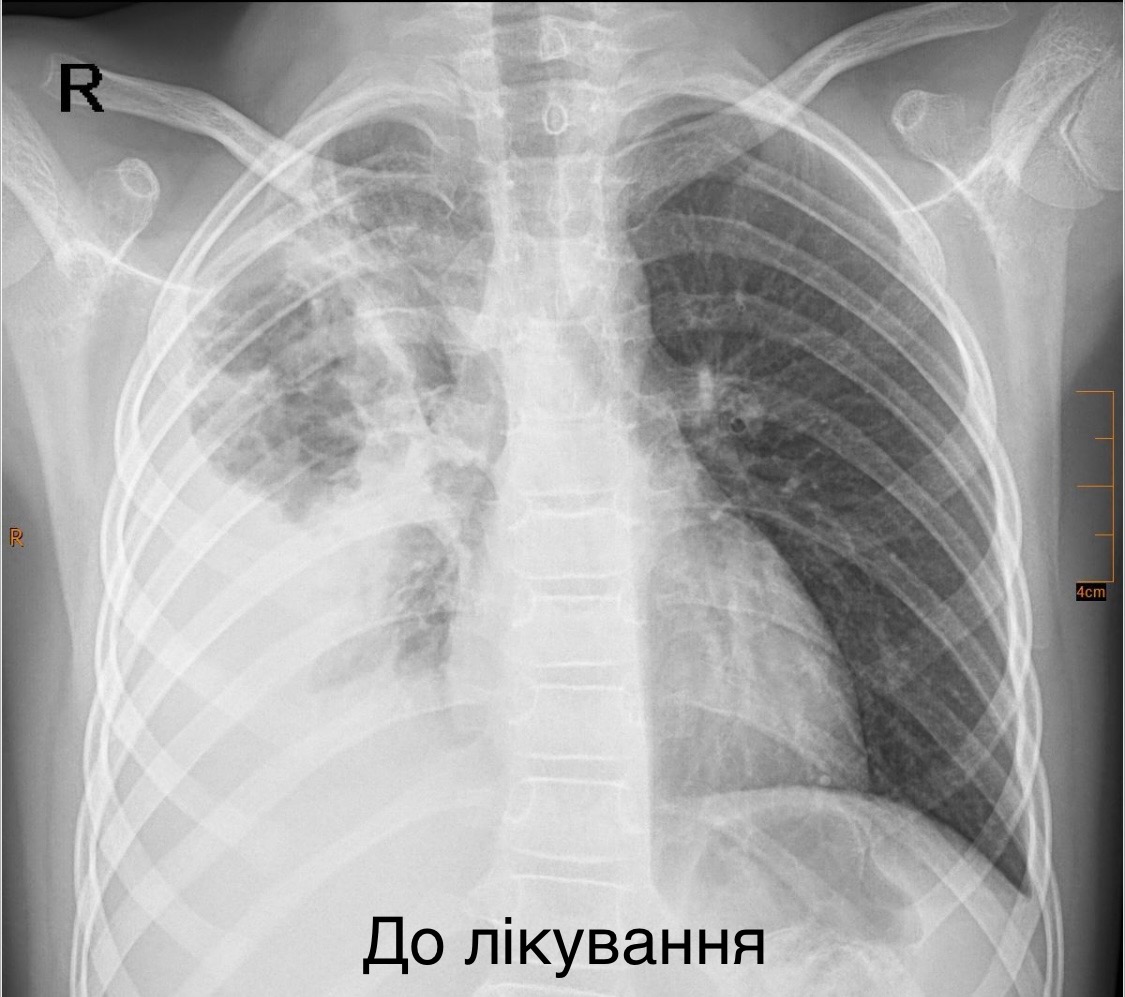

Львівські хірурги врятували 7-річну дівчинку з важкою деструктивною пневмонією

Лікарям вдалося зберегти уражену легеню, зробивши два розрізи розміром менше одного сантиметра

У Львові медики врятували життя дитини, яку екстрено доставили у критичному стані з деструктивною пневмонією правої легені. Дівчинка була у важкому стані: мала високу температуру тіла, задишку та низьку сатурацію кисню у крові. Про це повідомила Лікарня “Охматдит” у п’ятницю, 21 листопада.

7-річну пацієнтку одразу госпіталізували до клініки торакальної хірургії. Медики розпочали інтенсивну терапію, призначивши два сильні антибіотики, інфузійну та кисневу підтримку. Медична команда виконала тораскопічну операцію — малоінвазивне втручання, яке дозволило зберегти легеню.

“Лише через 2 розрізи розміром до 1 см ми дісталися до ураженої легені, усунули гнійно-некротичні вогнища і зберегли легеню”, — зазначив торакальний хірург Олександр Колодій.

Зараз дівчинка самостійно дихає та активно відновлюється.